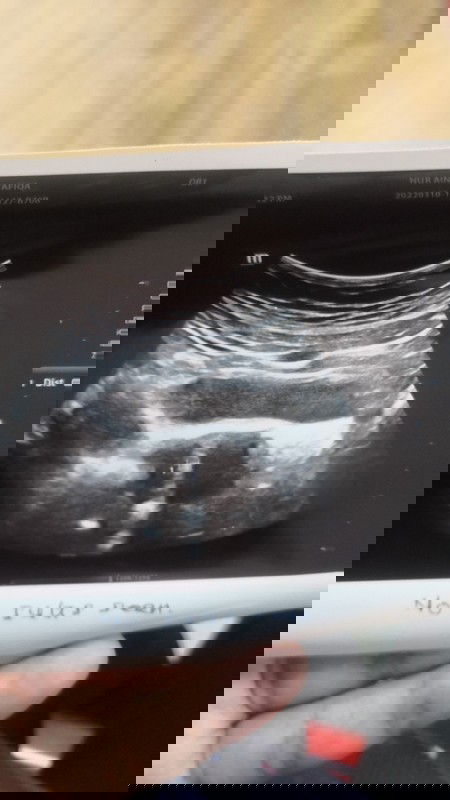

Scan and rujuk

Hi mum nak tanya, kalau dalam gambar scan yang macam ni nak kata dah gugur ke masih baru nak jadi, tebal dinding rahim 0.41cm, sebab sy ada kembung kembung perut, and ada rasa cramp2.. Pergi cek dr, dr scan nampak dinding rahim macam ni #pleasehelp